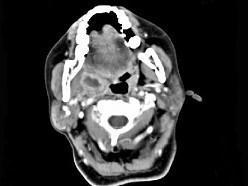

问题 女,52岁,咽喉部疼痛半个月,伴低热,CT如图所示,可能诊断为 ( )

选项 A、咽旁淋巴瘤 B、咽旁转移癌 C、咽部神经鞘瘤 D、鼻咽血管纤维瘤 E、咽旁脓肿

答案 E